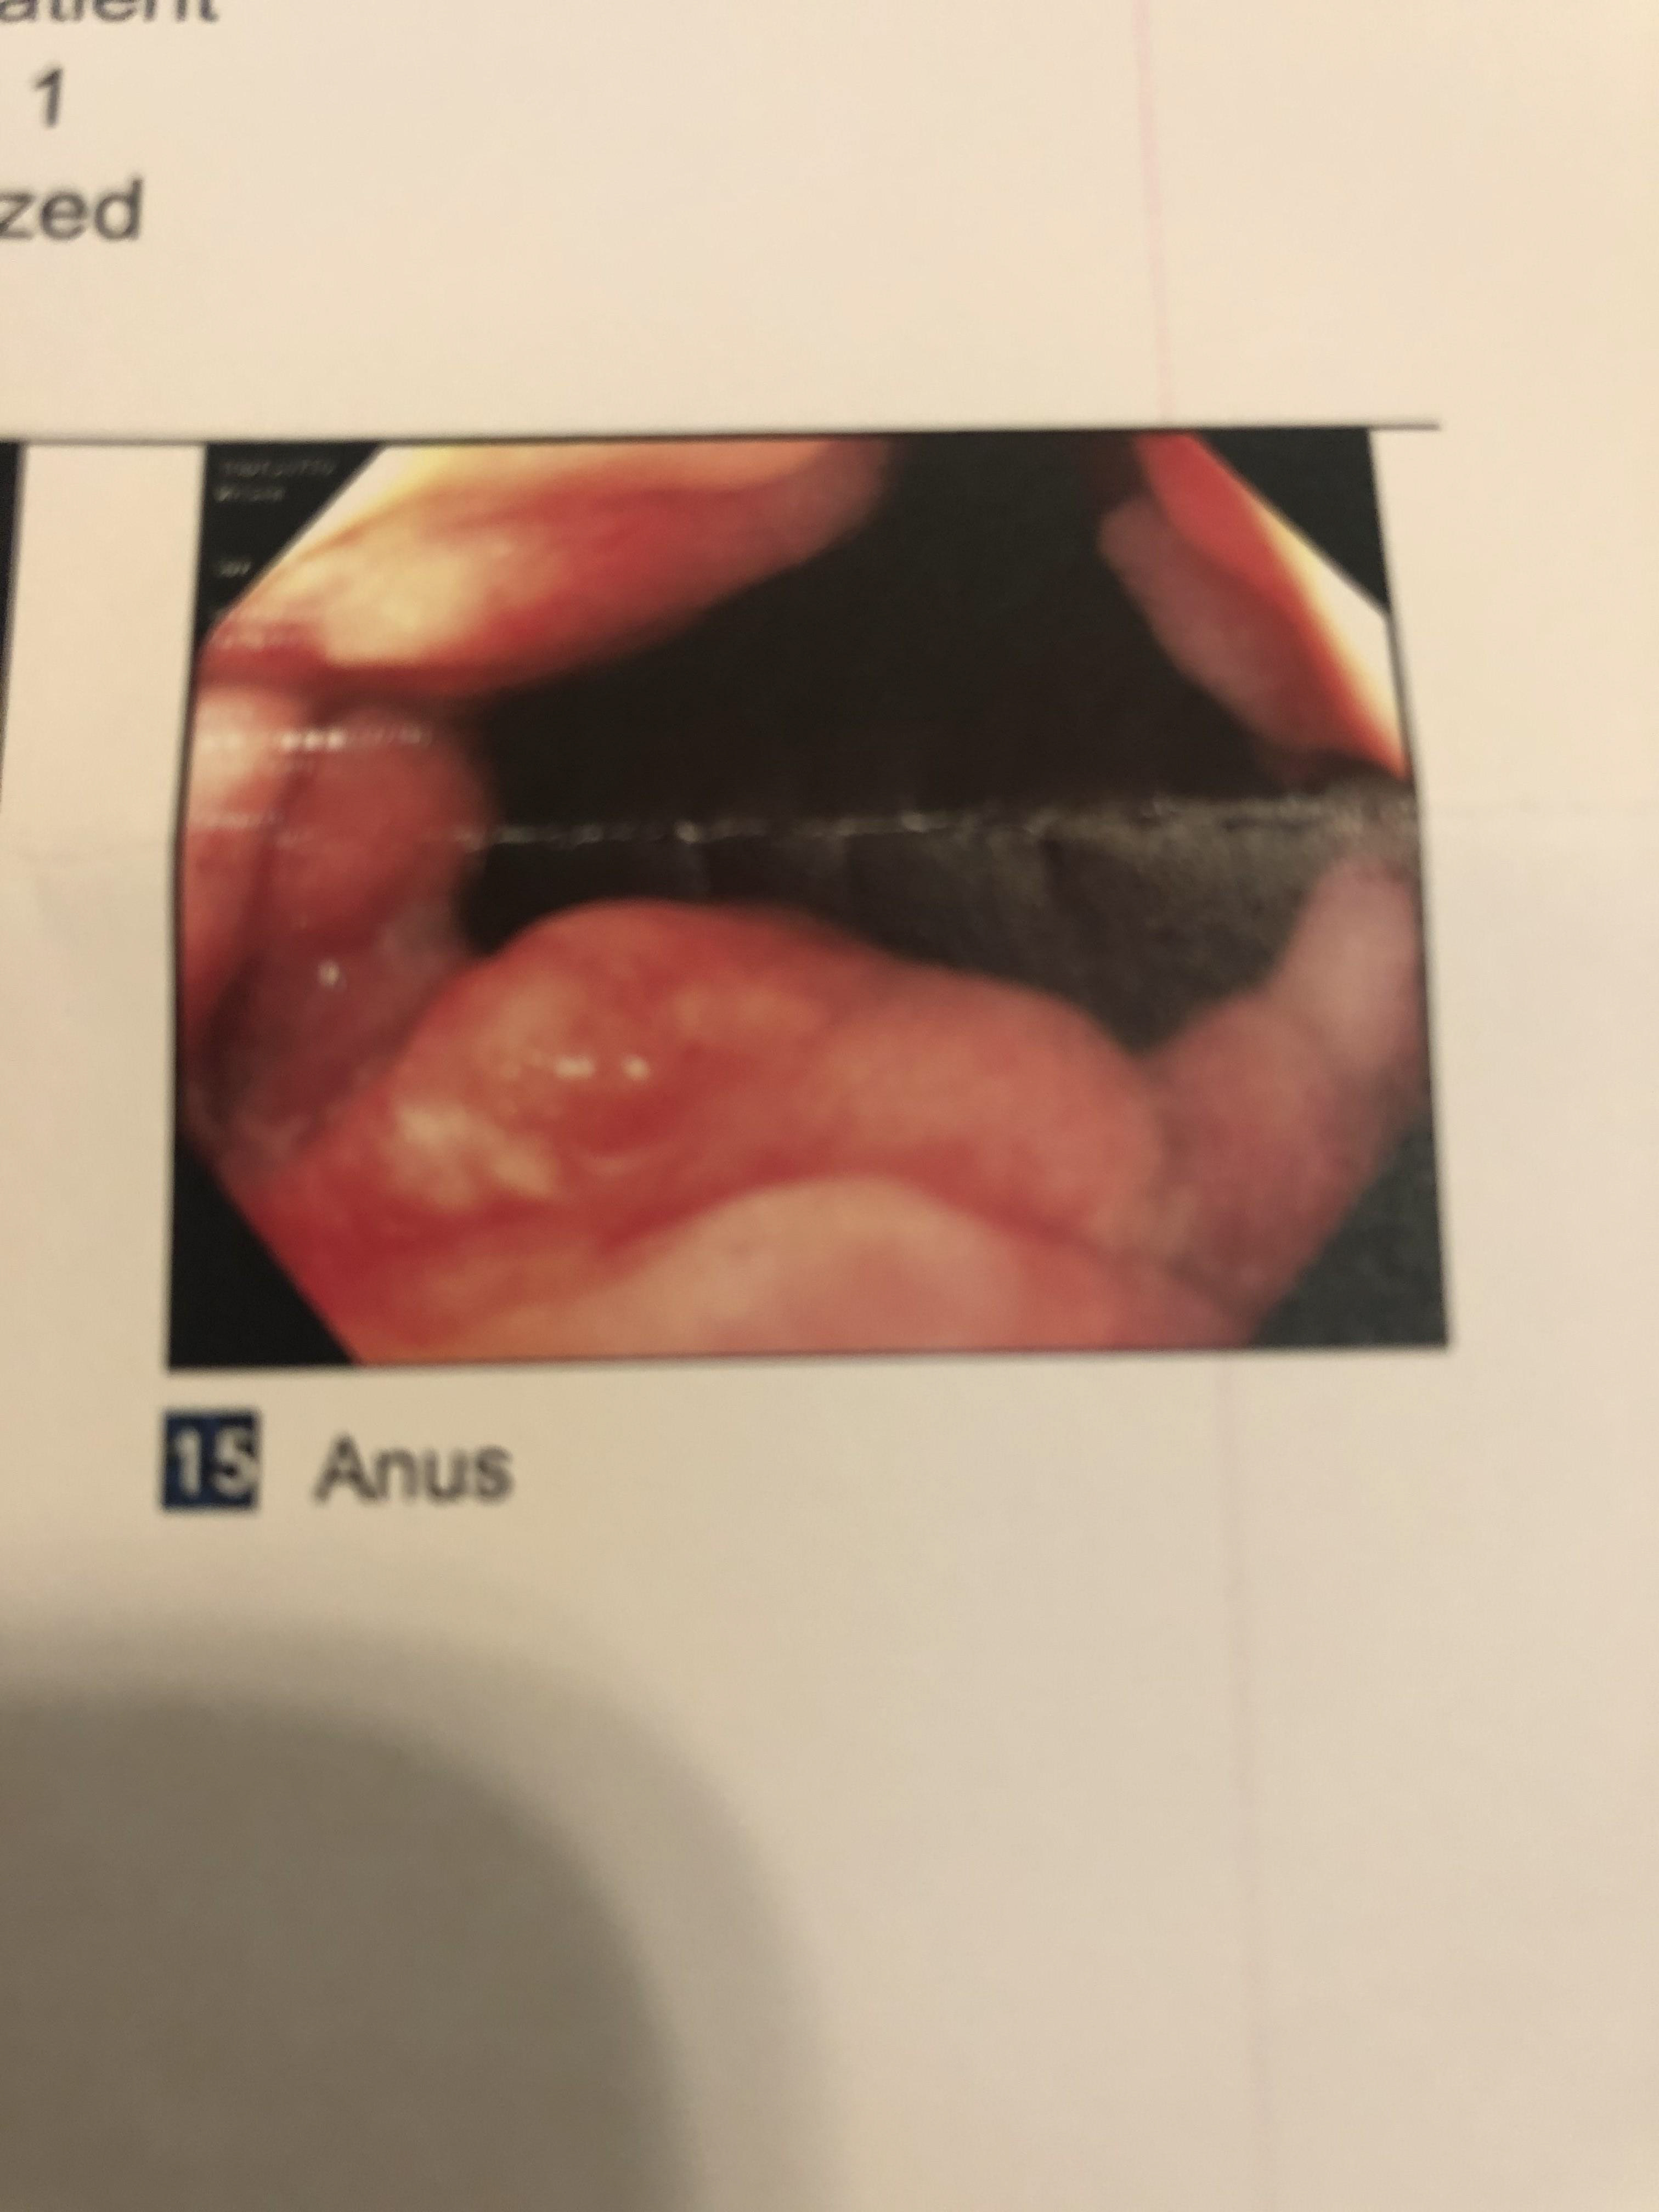

I developed a horrible anal fissure prior to my departure to Japan that made my experience in Naoshima indescribably painful. The goal of this study was to filter the experience of my anal fissure, realized as photos from a subsequent colonoscopy, through the parallel experience of Tadao Ando's structure.

Next, I created a simple collage of photos from my colonoscopy based on Chichu's topology.